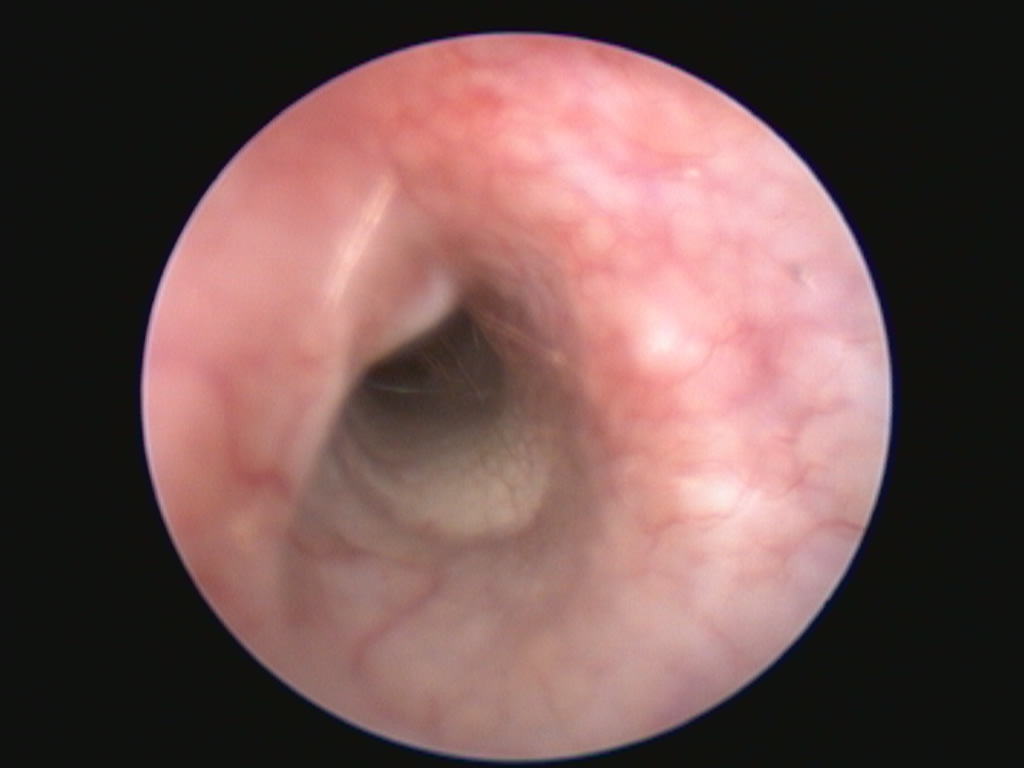

Video-Otoskop

Video-Otoskop Aufnahme

Untersuchung mit dem Video-Otoskop